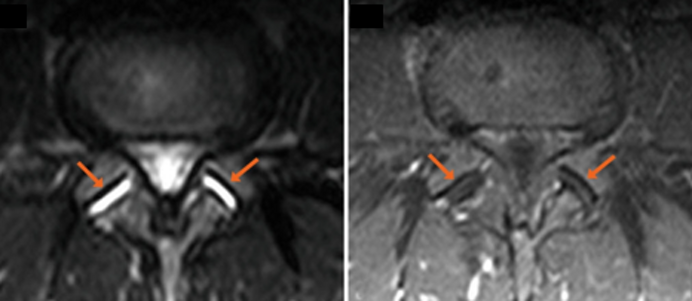

La conferma diagnostica arriva dalla indispensabile risonanza magnetica: si va dai reperti di sinovite fino ai più avanzati stadi di osteartrite di più faccette.

A complicare però il tutto è la possibilità di una mancata correlazione tra quadro clinico e quadro radiologico e quindi la possibile esistenza di una sindrome faccettale in assenza di un quadro radiologico tipico.

Soprattutto in questi casi l’opera dello specialista si rivela determinante nel stilare una corretta diagnosi e nel portare a termine la terapia efficace.